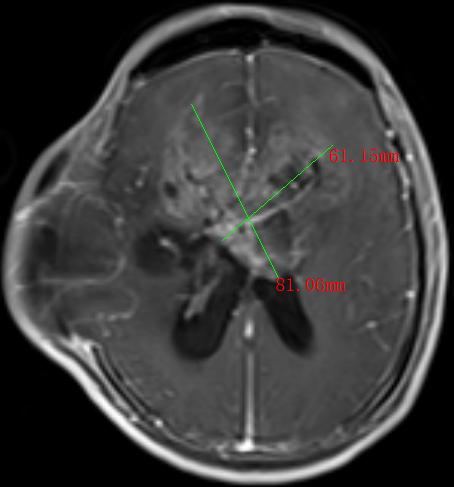

2022年,30多岁的张先生和40岁岁的李先生,均出现神志模糊或不清,并有反复癫痫发作的情况,经过当地医院检查,张先生和李先生分别诊断为松果体肿瘤、间变型星形细胞瘤术后复发并多发种植转移,两人颅内肿瘤直径分别达4.0cm和9.8cm。由于两人颅内肿瘤太大,辗转多家医院求医未果,正当两家人要放弃的时候,听朋友介绍瑞康医院射波刀治疗恶性肿瘤的效果非常不错,两家人怀着试一试的心态来到瑞康医院肿瘤科一区。

间变型星形细胞瘤术后复发并多发种植转移MRI影像